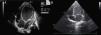

On admission he was apyretic, with pulse 190 bpm, respiratory rate 70–80 breaths per minute and oxygen saturation 95% in room air. His body weight was 6 kg (50th percentile). Physical examination revealed an infant of normal appearance but irritable and in respiratory distress. He was tachycardic, with an S3/S4 gallop rhythm. There were moist rales in the lung fields and chest wall retraction. The abdominal exam revealed hepatomegaly. The extremities displayed cyanosis and poor perfusion, with no edema. The chest X-ray showed cardiomegaly (cardiothoracic ratio 0.8) with pulmonary congestion (Figure 1A). The echocardiogram revealed a markedly enlarged left ventricular (LV) cavity with hypokinetic ventricular wall motion. LV end-diastolic diameter was 45 mm, LV end-systolic diameter was 40 mm, and fractional shortening (FS) was 5%, with no structural abnormalities (Figure 2). Electrocardiography showed sinus tachycardia (heart rate 190 bpm), LV hypertrophy and normal QTc.

Decreased serum calcium levels remained an issue while in the intensive care unit, requiring calcium boluses and drips to improve levels, which led us to study the patient's phosphorus–calcium metabolism. Hormone levels that were changed included elevated parathyroid hormone (231.8 pg/ml, reference value: 12–80 pg/ml), decreased 25-hydroxyvitamin D (5.94 ng/ml, reference value 11–70 ng/ml) and decreased 1,25 (OH)2 vitamin D3 (18.57 pg/ml, reference value: 20.2–46.2 pg/ml). There were no metabolic disorders on amino acid and organic acid tests. Calcium and vitamin D deficiency was confirmed and replacement with calcium and alfacalcidol (0.05 μg/kg/day) was started. As the levels of serum calcium increased to normal, the patient showed rapid recovery of cardiac function, normalization of LV dimensions and function on echocardiogram (Figure 3) and reduction of cardiomegaly on chest X-ray (Figure 1B). As the infant improved clinically, he was weaned to oral captopril, furosemide, spironolactone and digoxin. He was discharged on the 25th hospital day and followed in the outpatient clinic, with calcium gluconate and calcitriol replacement.